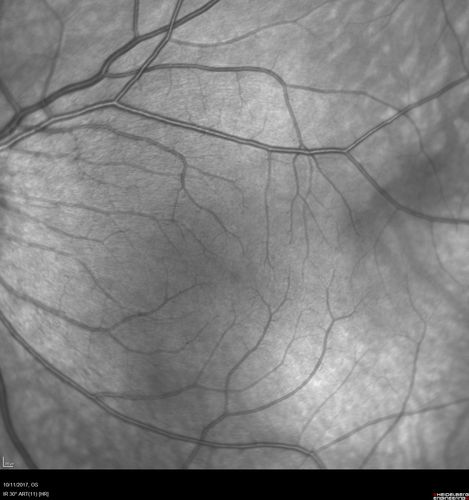

Foveal Hypoplasia in adult with ROP - good Vision

26 year old female Born at 1 lb 15 oz and had cryo for ROP at birth.

VA OD: Dcc20/25

VA OS: Dcc20/20

SD OCT shows foveal hypoplasia

The SD OCT scan shows incursion of one or more of the plexiform layers into the center of the fovea.